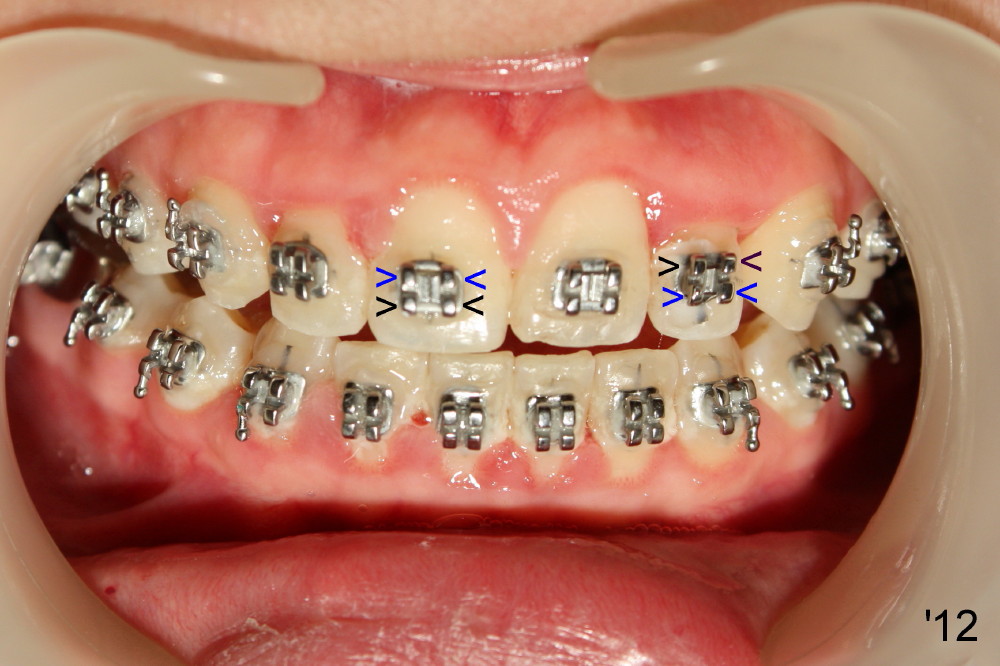

Fig.12: One month of UL bracketing (upside down), UL2 orientation is right. It does not require torque.

Normally the lower wings of upper anterior bracket (Fig.'12: UR1 black arrowheads) are wider than the lower wings (blue arrowheads).

In order to reduce the chance of needing torque after correction of the anterior cross bite, the bracket of UL2 is upside down, i.e., the wide wings are on the top, the narrow wing on the bottom.